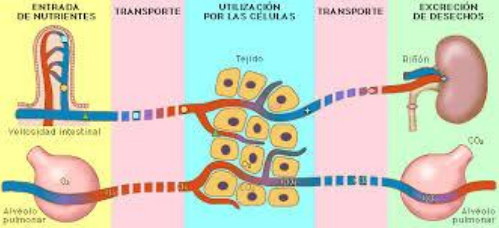

Esquema:

nutrientes y tóxicos - células -

órganos de purificación

|

Desintoxicación esquema 01 con nutrición y aire

[1]

|

Desintoxicación

1: de nutrientes

Comer - estómago+intestino - la sangre se toma

nutrientes - la sangre transporta desechos a los

riñones.

Desintoxicación 2: del aire

Respirar - pulmones - la sangre se toma

nutrientes - espirar los desechos.